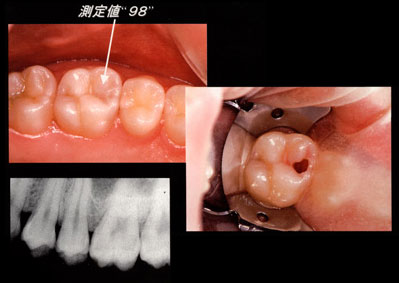

視診では発見しづらい象牙質に広がったカリエスです

(hidden caries)。

ダイアグノデントで咬合面を測定すると「98」と非常に高い数値を示したため切削すると中はカリエスで空洞化していました。